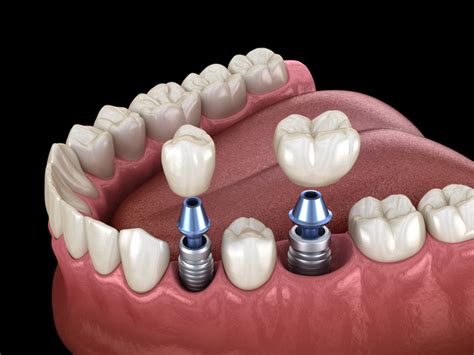

Platform Switching: Minimizando la Reabsorción Ósea

Por otro lado, se han realizado esfuerzos para evitar la pérdida de la cresta ósea periimplantaria en el momento de colocar un implante; recientemente se introdujo en la implantología oral el concepto de cambio de plataforma o platform switching, que consiste en el uso de un pilar de diámetro inferior que el de la plataforma del implante. Con esto se intenta minimizar la reabsorción ósea crestal que se produce al alejar la unión implante-muñón del hueso periimplantario, con las consiguientes ventajas de un ancho biológico periimplantario más largo, distanciamiento del componente bacteriano y una estabilidad del tejido marginal periimplantario.

Un concepto que no debemos obviar en la implantología oral es que toda colocación de implantes debe ser guiada por la prótesis, no el implante guiar la prótesis. La colocación tridimensional del implante comprende zonas de confort para la estabilidad a largo plazo del implante y los tejidos circundantes.